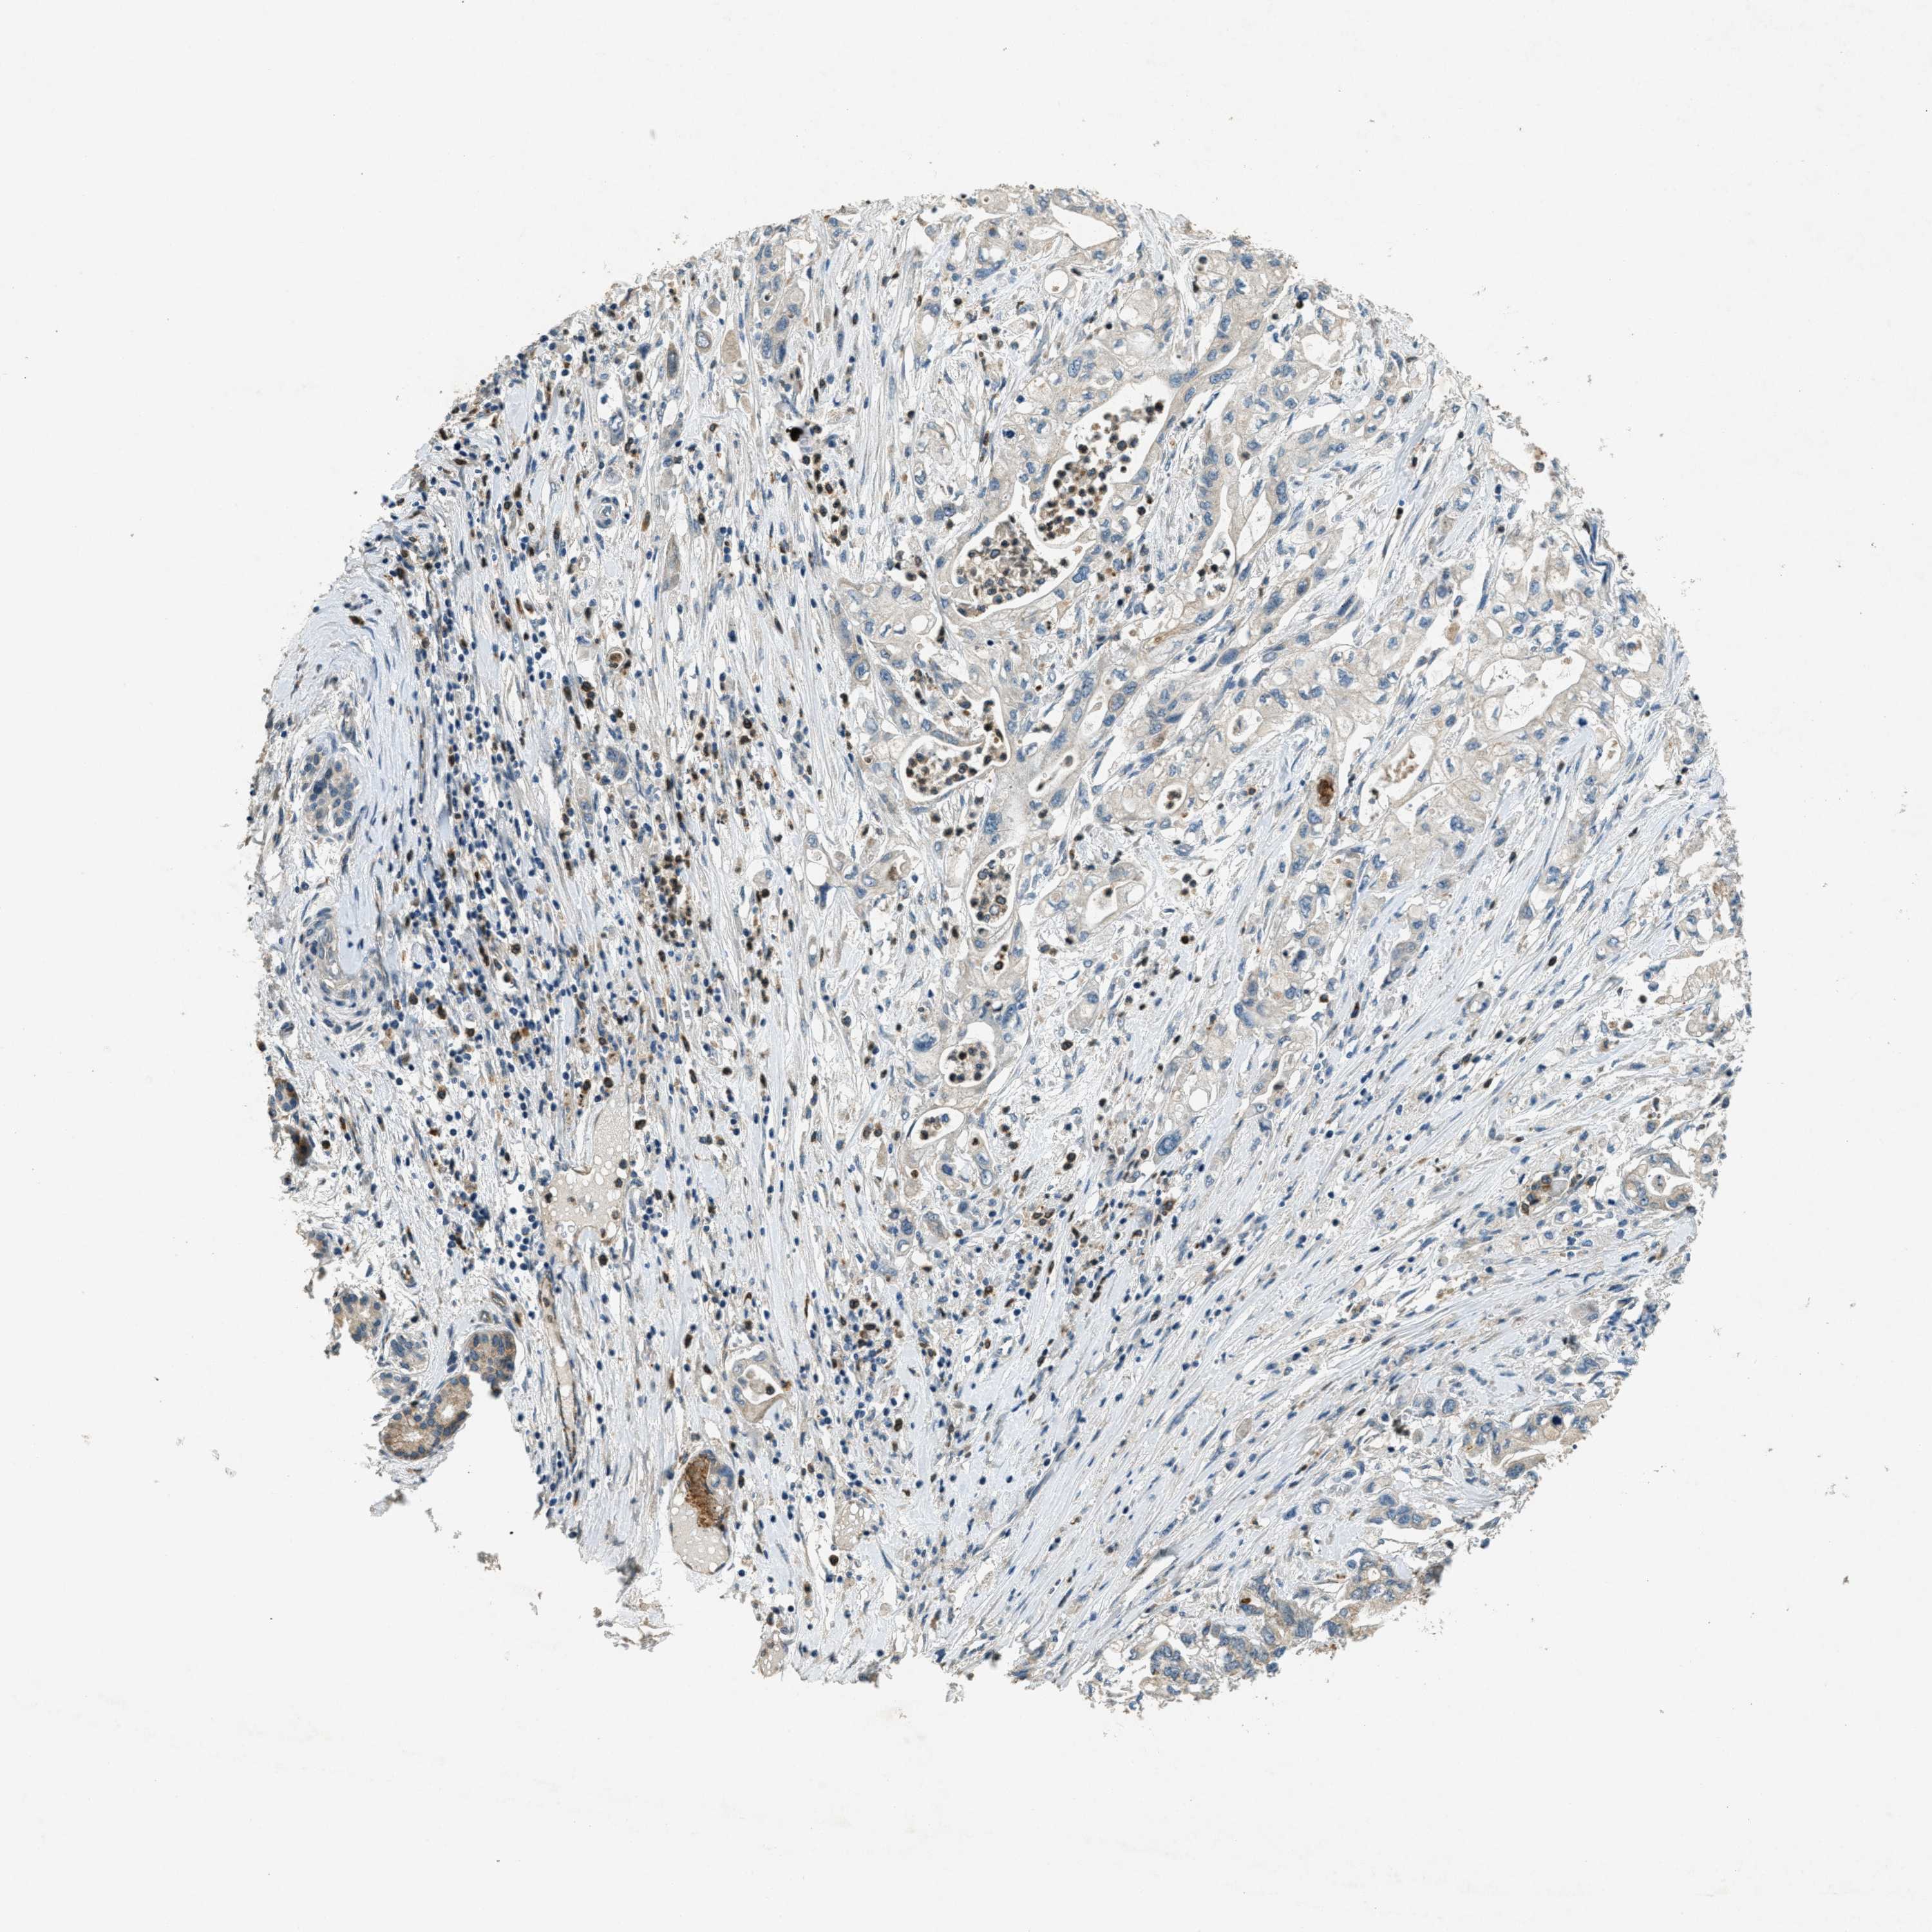

PANCREATIC CANCER - Protein expressioni

A mouse-over function shows sample information and annotation data. Click on an image to view it in a full screen mode. Samples can be filtered based on level of antibody staining by selecting one or several of the following categories: high, medium, low and not detected. The assay and annotation is described here.

Note that samples used for immunohistochemistry by the Human Protein Atlas do not correspond to samples in the TCGA dataset.

Antibody stainingi

Antibody staining in the annotated cell types in the current human tissue is reported as not detected, low, medium, or high, based on conventional immunohistochemistry profiling in selected tissues. This score is based on the combination of the staining intensity and fraction of stained cells.

Each image is clickable and will lead to virtual microscopy that enables deeper exploration of all samples and also displays staining intensity scores, fraction scores and subcellular localization as well as patient and tissue information for each sample.

Antibody CAB018067

Staining

High

Medium

Low

Not detected

Intensity

Strong

Moderate

Weak

Negative

Quantity

>75%

75%-25%

<25%

None

Location

Nuclear

Cytoplasmic/membranous

Cytoplasmic/membranous,nuclear

Adenocarcinoma, NOS

Adenocarcinoma, metastatic, NOS